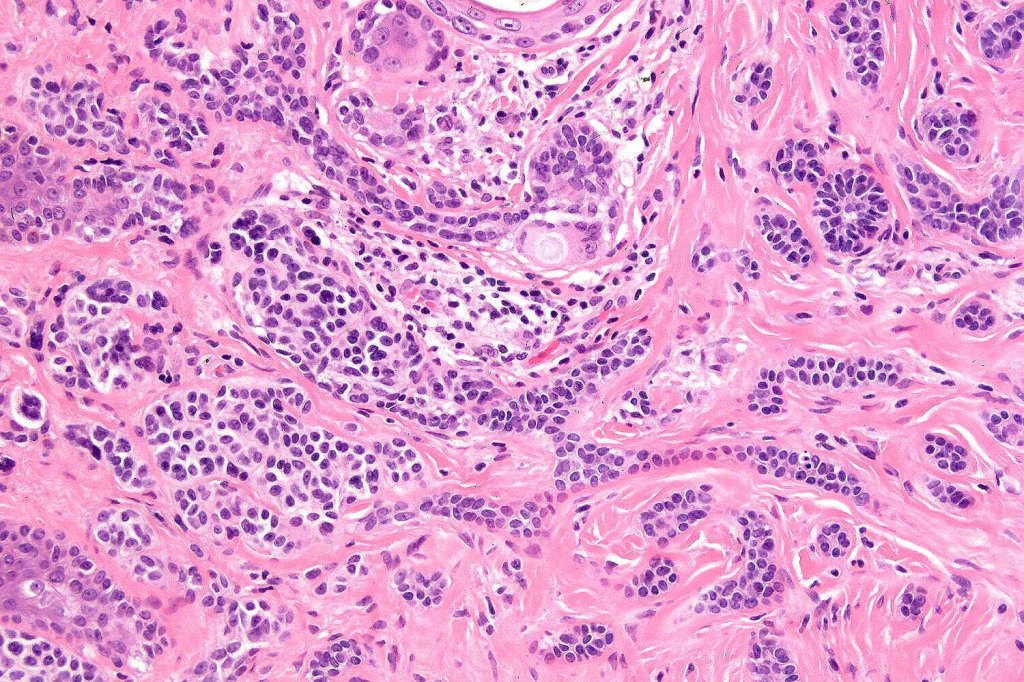

Histological features

•Consists of narrow epithelial strands & keratocysts embedded in a dense stroma

•No evidence of glandular differentiation

•Epithelial stands may arise from follicular epithelium

•Can rarely see matricial differentiation